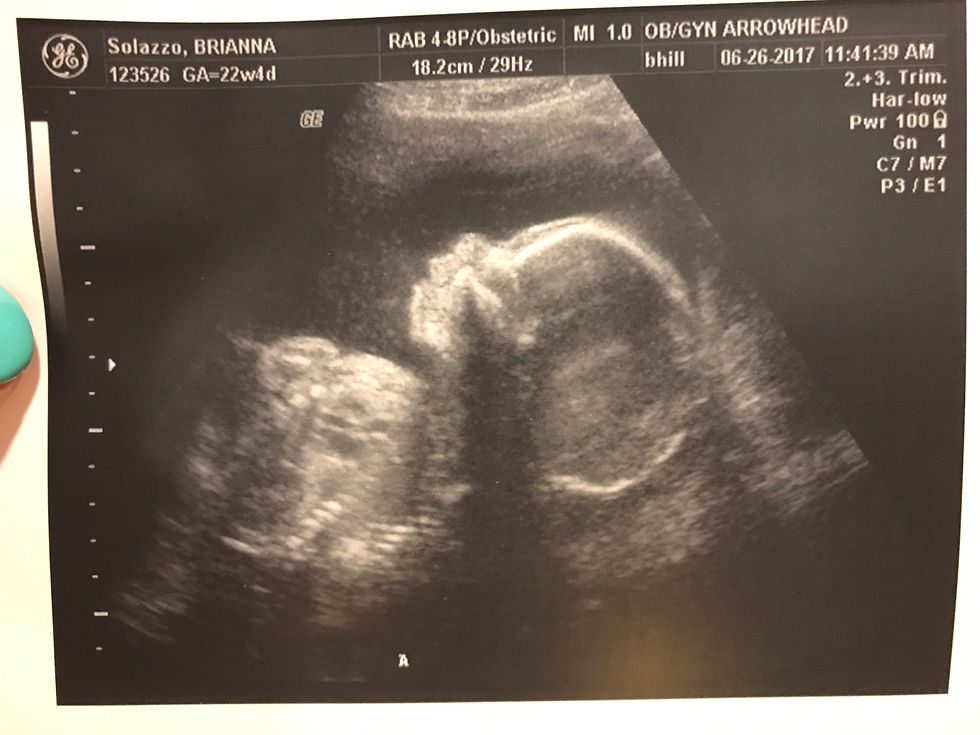

22 weeks

I am beginning to overheat! The weather outside is frightfully hot at 120 degrees and I can't get away from it. Sitting is starting to become very uncomfortable but standing hurts my back - Oh the joys! Kicks are at an all time high frequency and I couldn't be happier. The boys were moving during their ultrasound today...Wyatt even folded himself like a taco!!